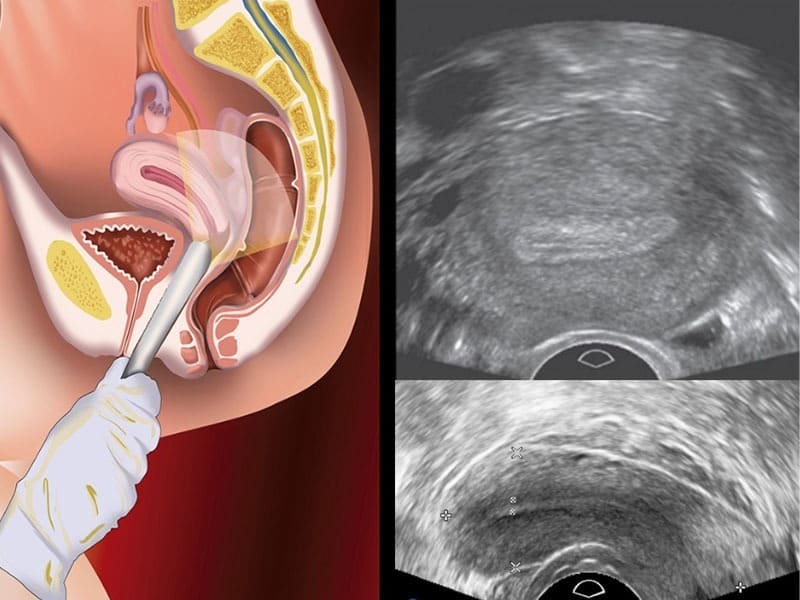

Siêu âm đầu dò (hay còn gọi là siêu âm đầu dò âm đạo) là phương pháp chẩn đoán hình ảnh sử dụng đầu dò chuyên dụng đưa vào trong âm đạo để quan sát rõ hơn các cơ quan sinh sản của nữ giới. Kỹ thuật này giúp bác sĩ đánh giá chi tiết tử cung, buồng trứng, vòi trứng, niêm mạc tử cung và phát hiện sớm các bất thường liên quan đến sức khỏe sinh sản. So với siêu âm bụng thông thường, siêu âm đầu dò cho hình ảnh rõ nét, chính xác hơn, đặc biệt hữu ích trong theo dõi rụng trứng, chẩn đoán u nang buồng trứng, u xơ tử cung hay nguyên nhân gây vô sinh hiếm muộn.

Siêu âm thai đầu dò là kỹ thuật quan trọng giúp bác sĩ quan sát rõ ràng tình trạng thai kỳ trong giai đoạn rất sớm, khi siêu âm bụng chưa cho hình ảnh rõ nét. Phương pháp này không chỉ hỗ trợ xác định thai có làm tổ đúng vị trí mà còn theo dõi sự phát triển ban đầu của phôi thai. Nhờ đó, mẹ bầu có thể yên tâm hơn về sức khỏe sinh sản của mình.

Đối với phụ nữ mang thai, siêu âm đầu dò là phương pháp có ý nghĩa quan trọng trong việc xác định thai kỳ sớm và phát hiện kịp thời các bất thường liên quan đến sức khỏe sinh sản. Ở giai đoạn 3 tuần tuổi, phôi thai vẫn đang trong quá trình di chuyển và làm tổ trong tử cung, kích thước còn quá nhỏ và chưa có hình dạng rõ ràng. Do đó, nếu siêu âm đầu dò ở thời điểm này thường rất khó quan sát túi thai, kết quả dễ thiếu chính xác và chưa thể khẳng định được thai đã phát triển ổn định.

Từ 5 – 6 tuần, phôi thai đã hình thành rõ ràng hơn, có thể quan sát được túi thai, phôi thai và thậm chí tim thai qua hình ảnh siêu âm đầu dò. Lúc này, bác sĩ có thể đánh giá được mức độ phát triển của thai nhi, đồng thời phát hiện sớm các dấu hiệu bất thường như thai ngoài tử cung, thai lưu hay nguy cơ sảy thai để kịp thời xử lý. Chính vì vậy, siêu âm đầu dò ở tuần thứ 5 được xem là an toàn, cần thiết và mang lại độ chính xác cao, giúp mẹ bầu yên tâm hơn trong giai đoạn đầu thai kỳ.